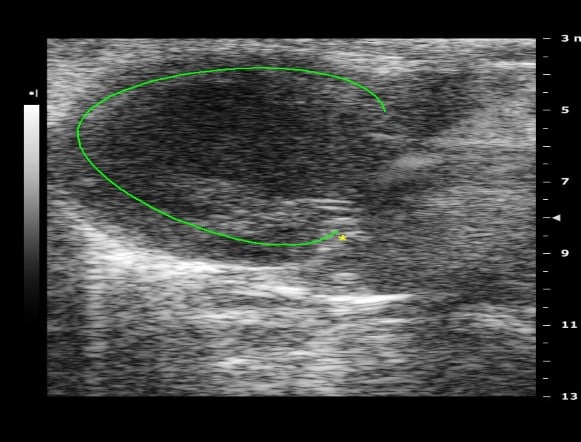

Day-14 Post operative Chronic MI